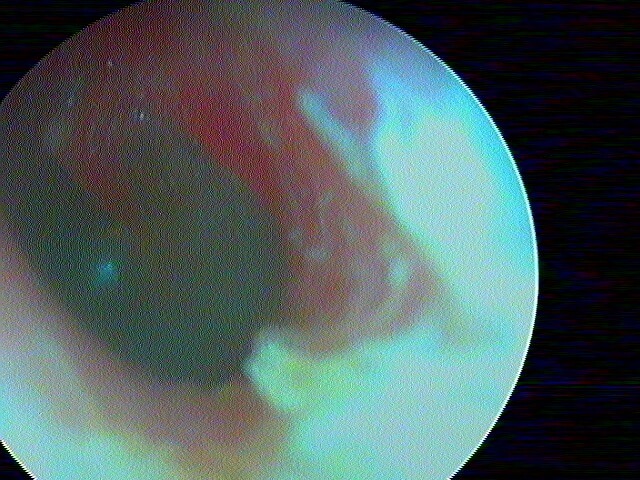

2/5 otite externe mycotique ou otomycose

Dans ma pratique, je vois plus d'otomycose à Aspergillus niger, très caractéristique avec ces points noirs.

La même oreille après aspiration: